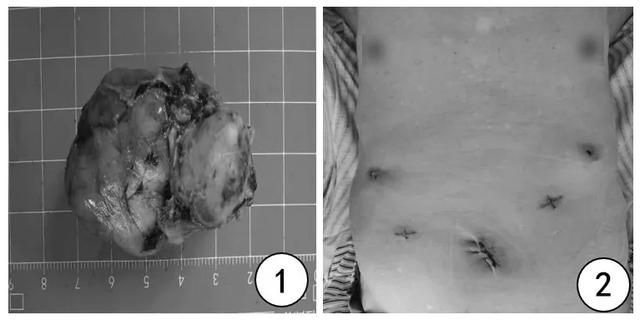

图 1:肿瘤完整取出体外,大小约 5 cm×3.5 cm×3 cm,图 2:腹部刀口,最长约 3 cm

此病例为高龄患者,瘤体较大(5 cm×3.5 cm×3 cm),且位于胃体小弯侧,与胰腺紧密相连,血管丰富,手术难度较大。如果单独用胃镜切除,创面巨大,不易缝合,而且瘤体无法完整取出,增加术后复发的风险;如果单独用腔镜切除,则术中瘤体定位困难,需要进行胃体的大部切除,且容易引起贲门口狭窄引起进食困难,手术创伤大,术后患者生活质量差,并发症多。